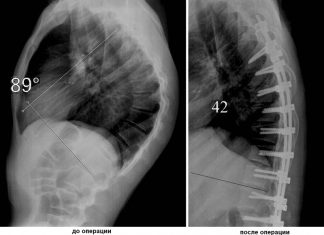

Болезнь Шейермана-Мау: концепция лечения

Дорзальный кифоз формируется в четырнадцать-шестнадцать лет. Распространенное заболевание характеризуется постепенным ис...